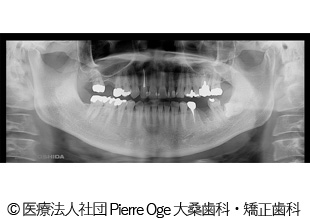

【症例1】左上456、右下6 インプラント治療

- 治療前

- 治療後

- 治療名

- 左上456、右下6 インプラント治療

- 費用

- 1,578,000円(税込)

- 費用の詳細

- 検査代:32,000円(税込)/手術代:759,000円(税込)/補綴代:787,000円(税込)

※当時の金額 - 期間

- 8ヵ月

- 通院回数

- 17回

- 性別・年齢

- 50代女性

治療内容

-

患者様の症状

噛むと痛い。歯根破折。インプラント治療希望でご来院されました。

治療方法

左上奥歯の歯根破折、欠損部に代わってインプラントを埋入。骨量が少なかったため同時に人工骨移植。その後、インプラントが安定してから被せ物を入れることで機能面・審美面の回復に繋がりました。

治療結果

歯根破折、欠損部を補うことができ、機能面・審美面の回復に繋がりました。

治療を行う上での注意点(リスク・副作用)

疼痛、腫脹、青アザ、出血、神経麻痺、鼻出血、補綴物の破損、インプラント体の破折、咬合違和感、インプラント周囲炎。